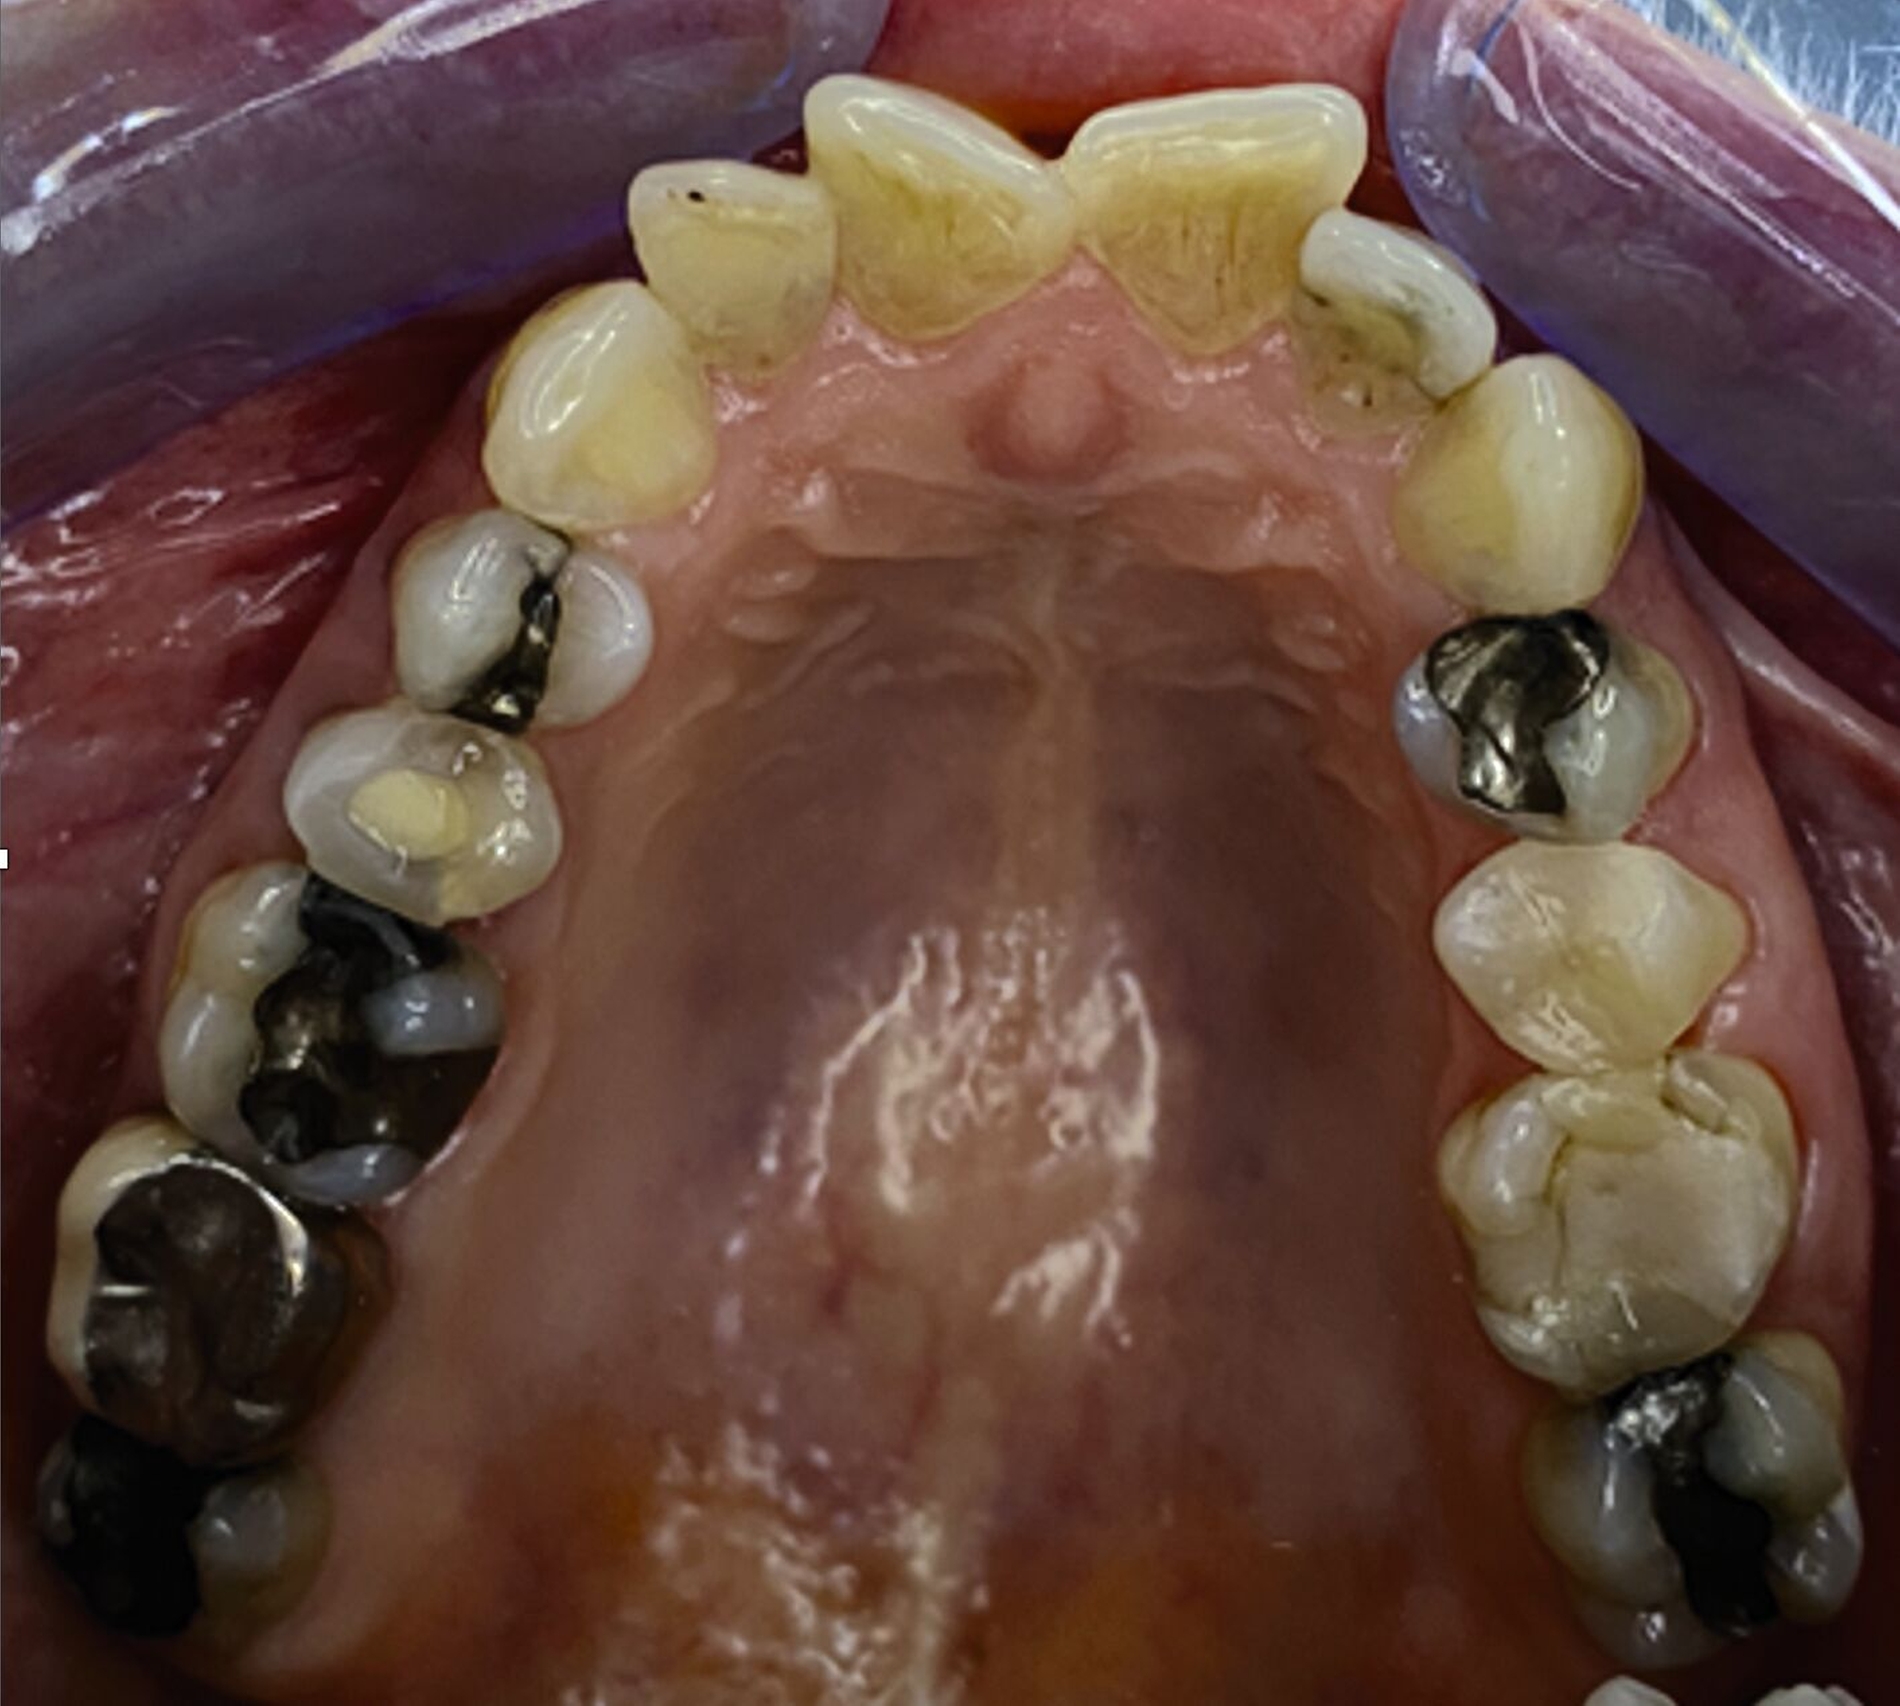

Klinisch zeigten sich diverse großflächig, mehrheitlich mit Amalgam gefüllte Seitenzähne, suffiziente endodontische Behandlungen an den Zähnen 16 und 14 sowie intakte Kronen an den Zähnen 16 und 48 (Abbildung 2). Ein Parodontaler Screening-Index (PSI) wurde erhoben (1-1-0-0-2-1), der stabile Verhältnisse nachwies. Das funktionelle CMD-Screening zeigte eine nicht-druckdolente Kaumuskulatur sowie eine uneingeschränkte Mundöffnung ohne Reiben und Knacken.

Tabelle 1 zeigt das entsprechende Befundschema mit den Taschentiefen mesial und distal, den Lockerungsgraden und den Sensibilitätsüberprüfungen mittels Kältespray (ViPr). Die Ruheschwebelage wurde mithilfe des Zielinsky-Zirkels auf 2 mm bestimmt. Die Nonokklusion im Seitenzahnbereich konnte auf circa 1,5 mm bemessen werden. Tabelle 2 spiegelt das entsprechende Okklusionsprotokoll wider. Das Okklusionsprofil wird auch in den Abbildungen 3a bis 3c deutlich.